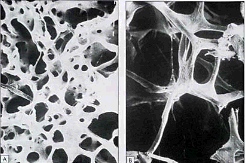

One important and often overlooked preventative health measure is awareness of your bone health. Your bone mineral density (BMD) is the standard indicator for the degree of bone mineral found in your body. Loss or decrease in bone mineral density can lead to increased susceptibility for bone fractures, especially of the hip, spine, and wrist; however, any bone can be affected. Even though many women develop osteoporosis, especially after menopause, men are not immune from suffering the consequences of this disease.

Of the more than 10 million Americans estimated to have osteoporosis, 2 million are men, and there may be almost 34 million people who have a low bone density disorder called osteopenia. One in two white women will experience an osteoporotic bone fracture in her lifetime. Surprisingly, millions of Americans remain undiagnosed due, most likely, to the lack of symptoms. More often than not, the initial symptom is a fracture.